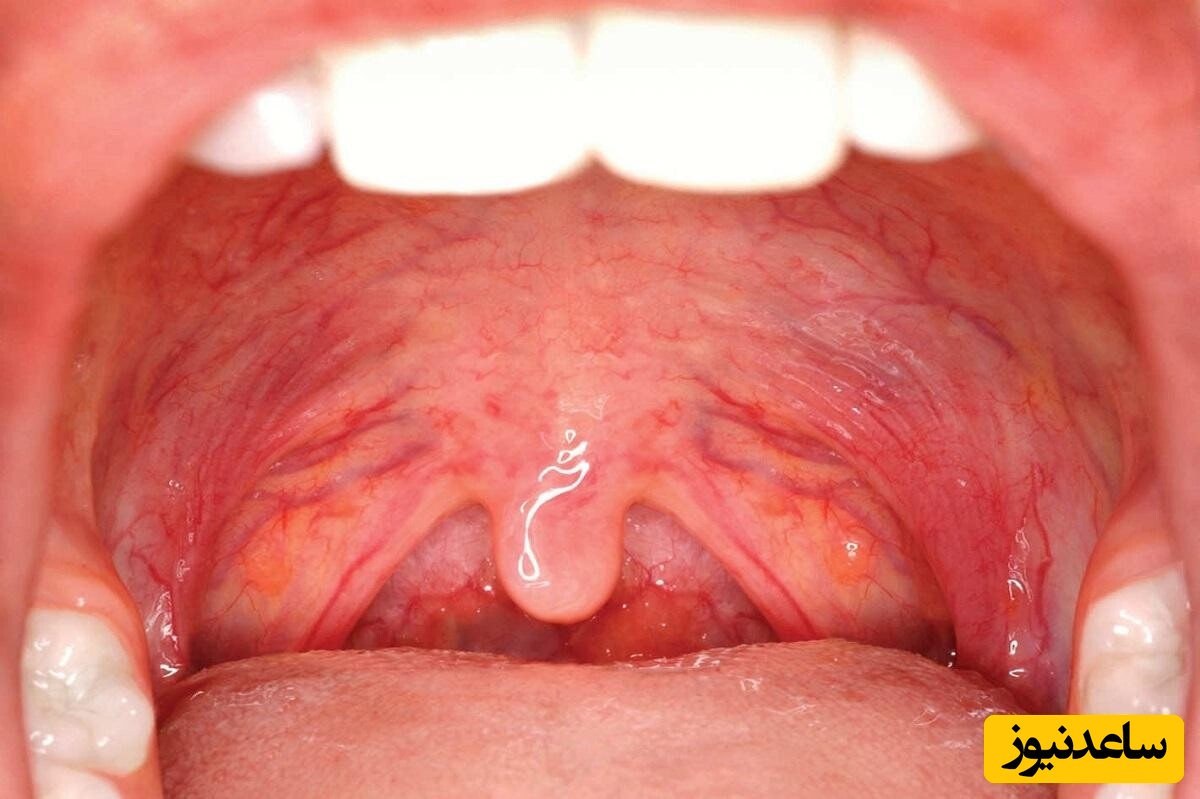

به گزارش سرویس دهان و دندان پایگاه خبری ساعدنیوز، تورم زبان کوچک یا اوولیت (Uvulitis) وضعیتی است که در آن زبان کوچک، یعنی بافت گوشتی آویزان در پشت گلو، ملتهب و متورم میشود. این مشکل میتواند ناشی از عفونتهای ویروسی یا باکتریایی، آلرژی، کمآبی، یا تحریککنندههایی مانند سیگار و الکل باشد. علائم آن شامل احساس گیر کردن چیزی در گلو، مشکل در بلع، گلودرد، و گاهی تب است. اگرچه در موارد شدید نیاز به مراجعه به پزشک است، اما انواع خفیف اوولیت را میتوان با روشهای خانگی مدیریت کرد. در این مقاله، 10 درمان خانگی معتبر و کاربردی برای کاهش تورم زبان کوچک ارائه میدهیم که بر اساس منابع علمی و تجربیات کاربران تهیه شدهاند.